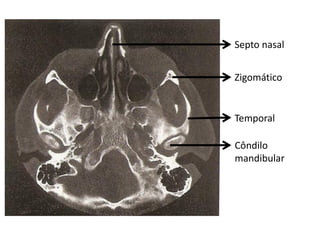

Tomografia Computadorizada do Crânio

• Alto grau de confiabilidade;

• Qualquer suspeita patológica envolvendo o encéfalo é indicativo de

TC;

Alterações visualizadas:

   Neoplasias;

   Lesões;

   Tumores

   Metástases;

   Hemorragia intracraniana;

   Aneurisma;

   Abscesso;

   Atrofia cerebral;

   Alterações pós-traumáticas;

   Alterações congênitas.

Septo nasal

Zigomático

Temporal

Côndilo

mandibular